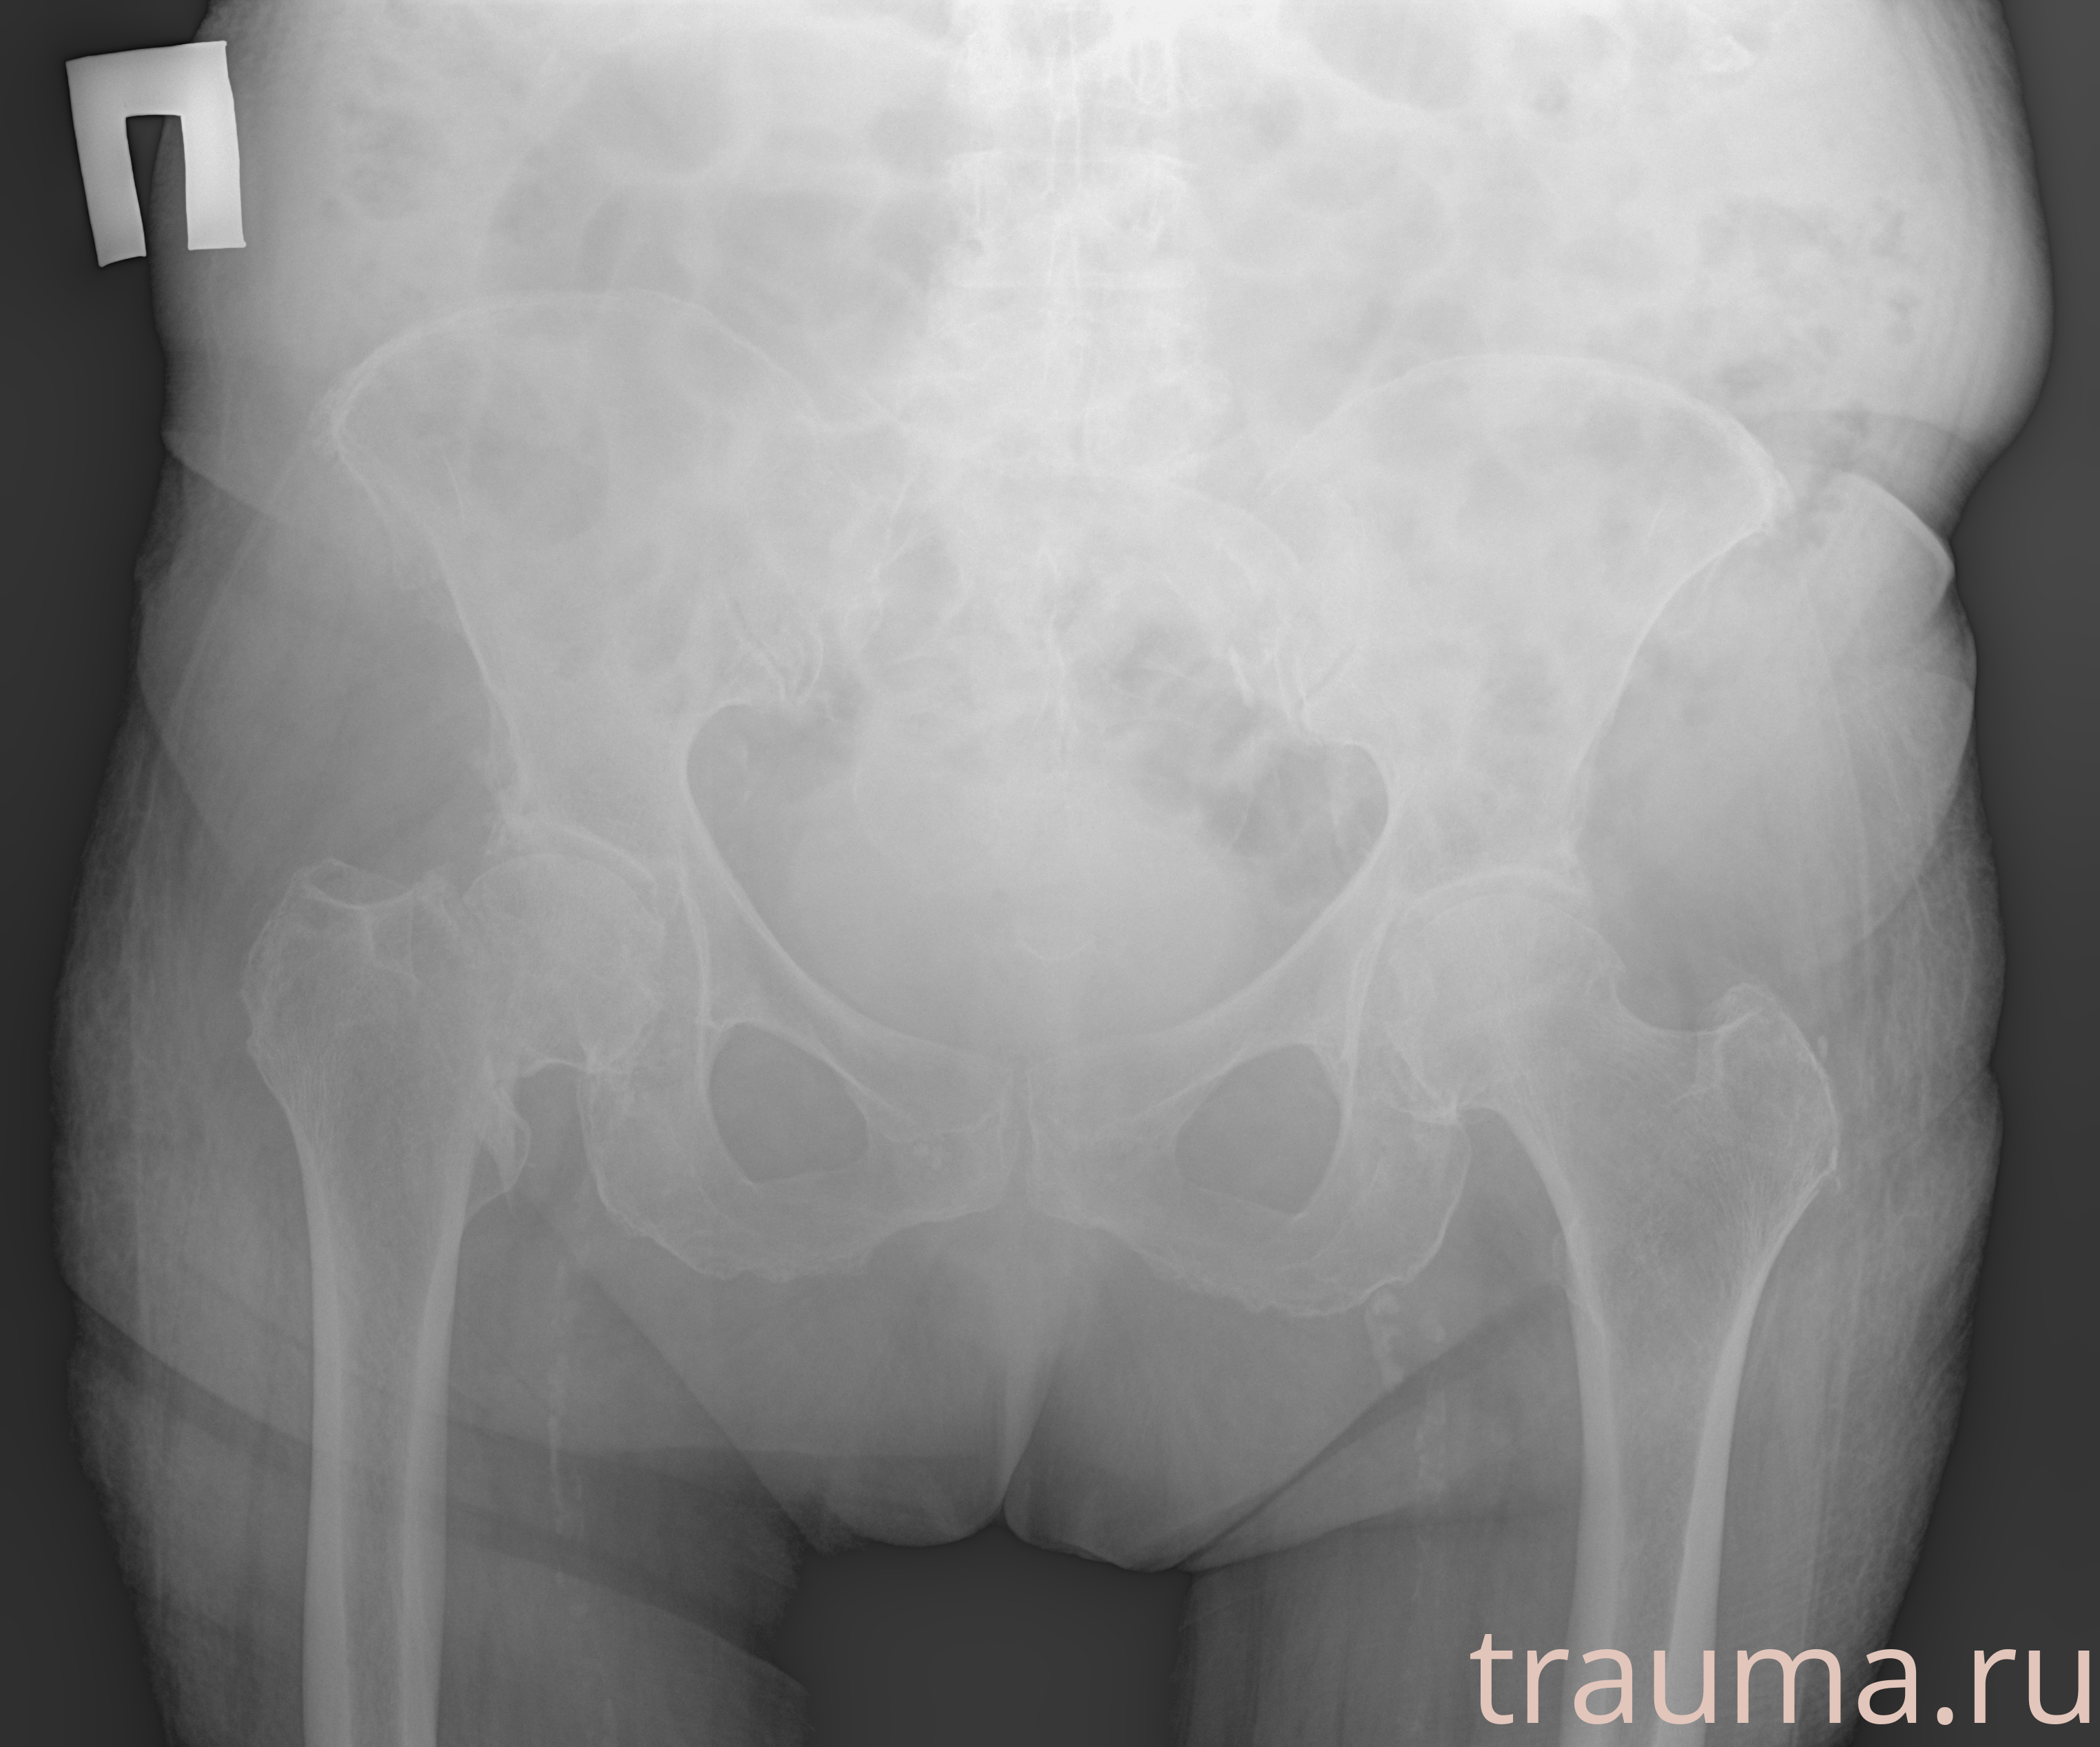

Первая помощь при переломе шейки бедра

Рентген на дому: по вашему адресу приезжает врач-рентгенолог, травматолог-ортопед с мобильным рентгеновским аппаратом, проводит диагностику травмы или заболевания, делает необходимые рентгенограммы, дает рекомендации по дальнейшему лечению. Получить качественные снимки в домашних условиях возможно благодаря уникальной методике, разработанной МосРентген Центром для института  Склифосовского